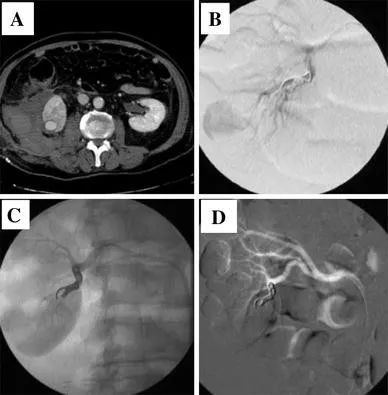

(3)延遲出血

延遲出血的其他原因是動靜脈瘻和動脈假性動脈瘤(圖 1)。這些併發症很少見,佔所有病例的 1.2% 。患者通常在經歷一個複雜多事的過程後出院,並在幾天甚至幾周後返回,抱怨持續性輕度血尿。該病的特徵是間歇性或持續性血尿、血紅蛋白緩慢下降,很少出現低血壓或肉眼血尿。腹部 CT 可證實診斷,應透過選擇性栓塞術進行治療 。

圖1 透過栓塞治療,右腎假性動脈瘤導致延遲出血和腎周血腫形成。a, b 栓塞前。c、d 栓塞後

包膜下腎或腎周血腫是非常罕見的出血併發症。它們大多是由於其他原因(例如,腎絞痛)在放射學評估後被意外診斷出來的,並且通常會順利消退 。CT 掃描也是區分血腫和尿腫的建議檢查。保守治療在大多數情況下是有效的,而很少需要介入措施(或放置經皮引流)。